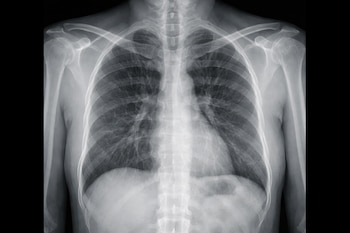

Ecografía (ultrasonido)

A diferencia de los rayos X, la ecografía no utiliza radiación, sino ondas sonoras de alta frecuencia, explica la Escuela de Salud de Murcia.

Un transductor emite ondas sonoras que rebotan al chocar con una interfaz de diferente densidad. El equipo calcula el tiempo que tarda el “eco” en volver y crea una imagen en tiempo real.

- Los objetos sólidos suelen ser hiperecogénicos (blancos).

- Un signo clave es la sombra acústica: el objeto bloquea el sonido y deja una “mancha negra” detrás de él, lo que confirma su presencia.

¿Qué detecta con precisión?

Es la herramienta reina para los objetos no metálicos y radiolúcidos:

- Madera y astillas: Es extremadamente sensible para detectar espinas o madera que los rayos X no ven.

- Plásticos: Juguetes o piezas pequeñas.

- Materia orgánica: Espinas de pescado o fragmentos vegetales.

Ventaja adicional: Permite ver la relación del objeto con vasos sanguíneos o tendones cercanos y guiar una cirugía de extracción en tiempo real.

¿Cuál es la más indicada?

La elección no siempre es excluyente; a menudo son complementarias.

- Si se sospecha que un niño tragó una moneda, la radiografía es el estándar de oro por su rapidez y claridad para objetos metálicos.

- Si una persona se clavó una astilla de madera en el pie y no se encuentra a simple vista, la ecografía es la única herramienta capaz de localizarla y medir a qué profundidad se encuentra.

Mientras que la radiografía domina el mundo de lo inorgánico y denso, la ecografía es la lupa de alta precisión para lo orgánico y lo sutil, permitiendo que los médicos actúen con total certeza antes de realizar cualquier incisión.